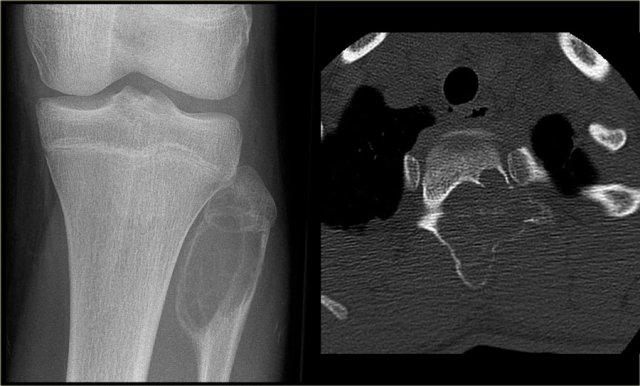

Chondromyxoid Fibroma

U xơ sụn nhầy là một tổn thương hiếm gặp.

U xơ sụn nhầy có hình ảnh tương tự u xơ không cốt hóa.

Vị trí ưu tiên: đầu gần xương chày và bàn chân.

Mặc dù tên gọi gợi ý rằng u xơ sụn nhầy là tổn thương sụn, nhưng thông thường không thấy hình ảnh vôi hóa.

Hình ảnh bên trái của một u xơ sụn dạng nhầy (CMF).

Có một tổn thương tiêu xương lệch tâm ở vùng hành xương của đầu gần xương chày.

Ở phía trong có một bờ xơ cứng.

Ở phía ngoài có sự phá hủy vỏ xương đều đặn với lớp xương ngoại vi.

Hình ảnh MRI cũng cho thấy bờ xơ cứng với cường độ tín hiệu thấp.

Discriminators :

- Mention when an NOF is mentioned.